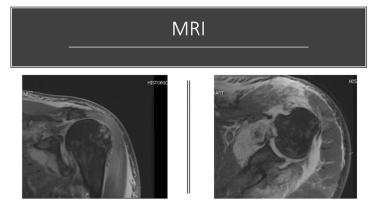

Anatomic & Reverse Shoulder Arthroplasty Case Review: TRUMATCH™ Personalized Solutions

Reverse Total Shoulder 3d Surgical Planning with Michael Codsi, MD